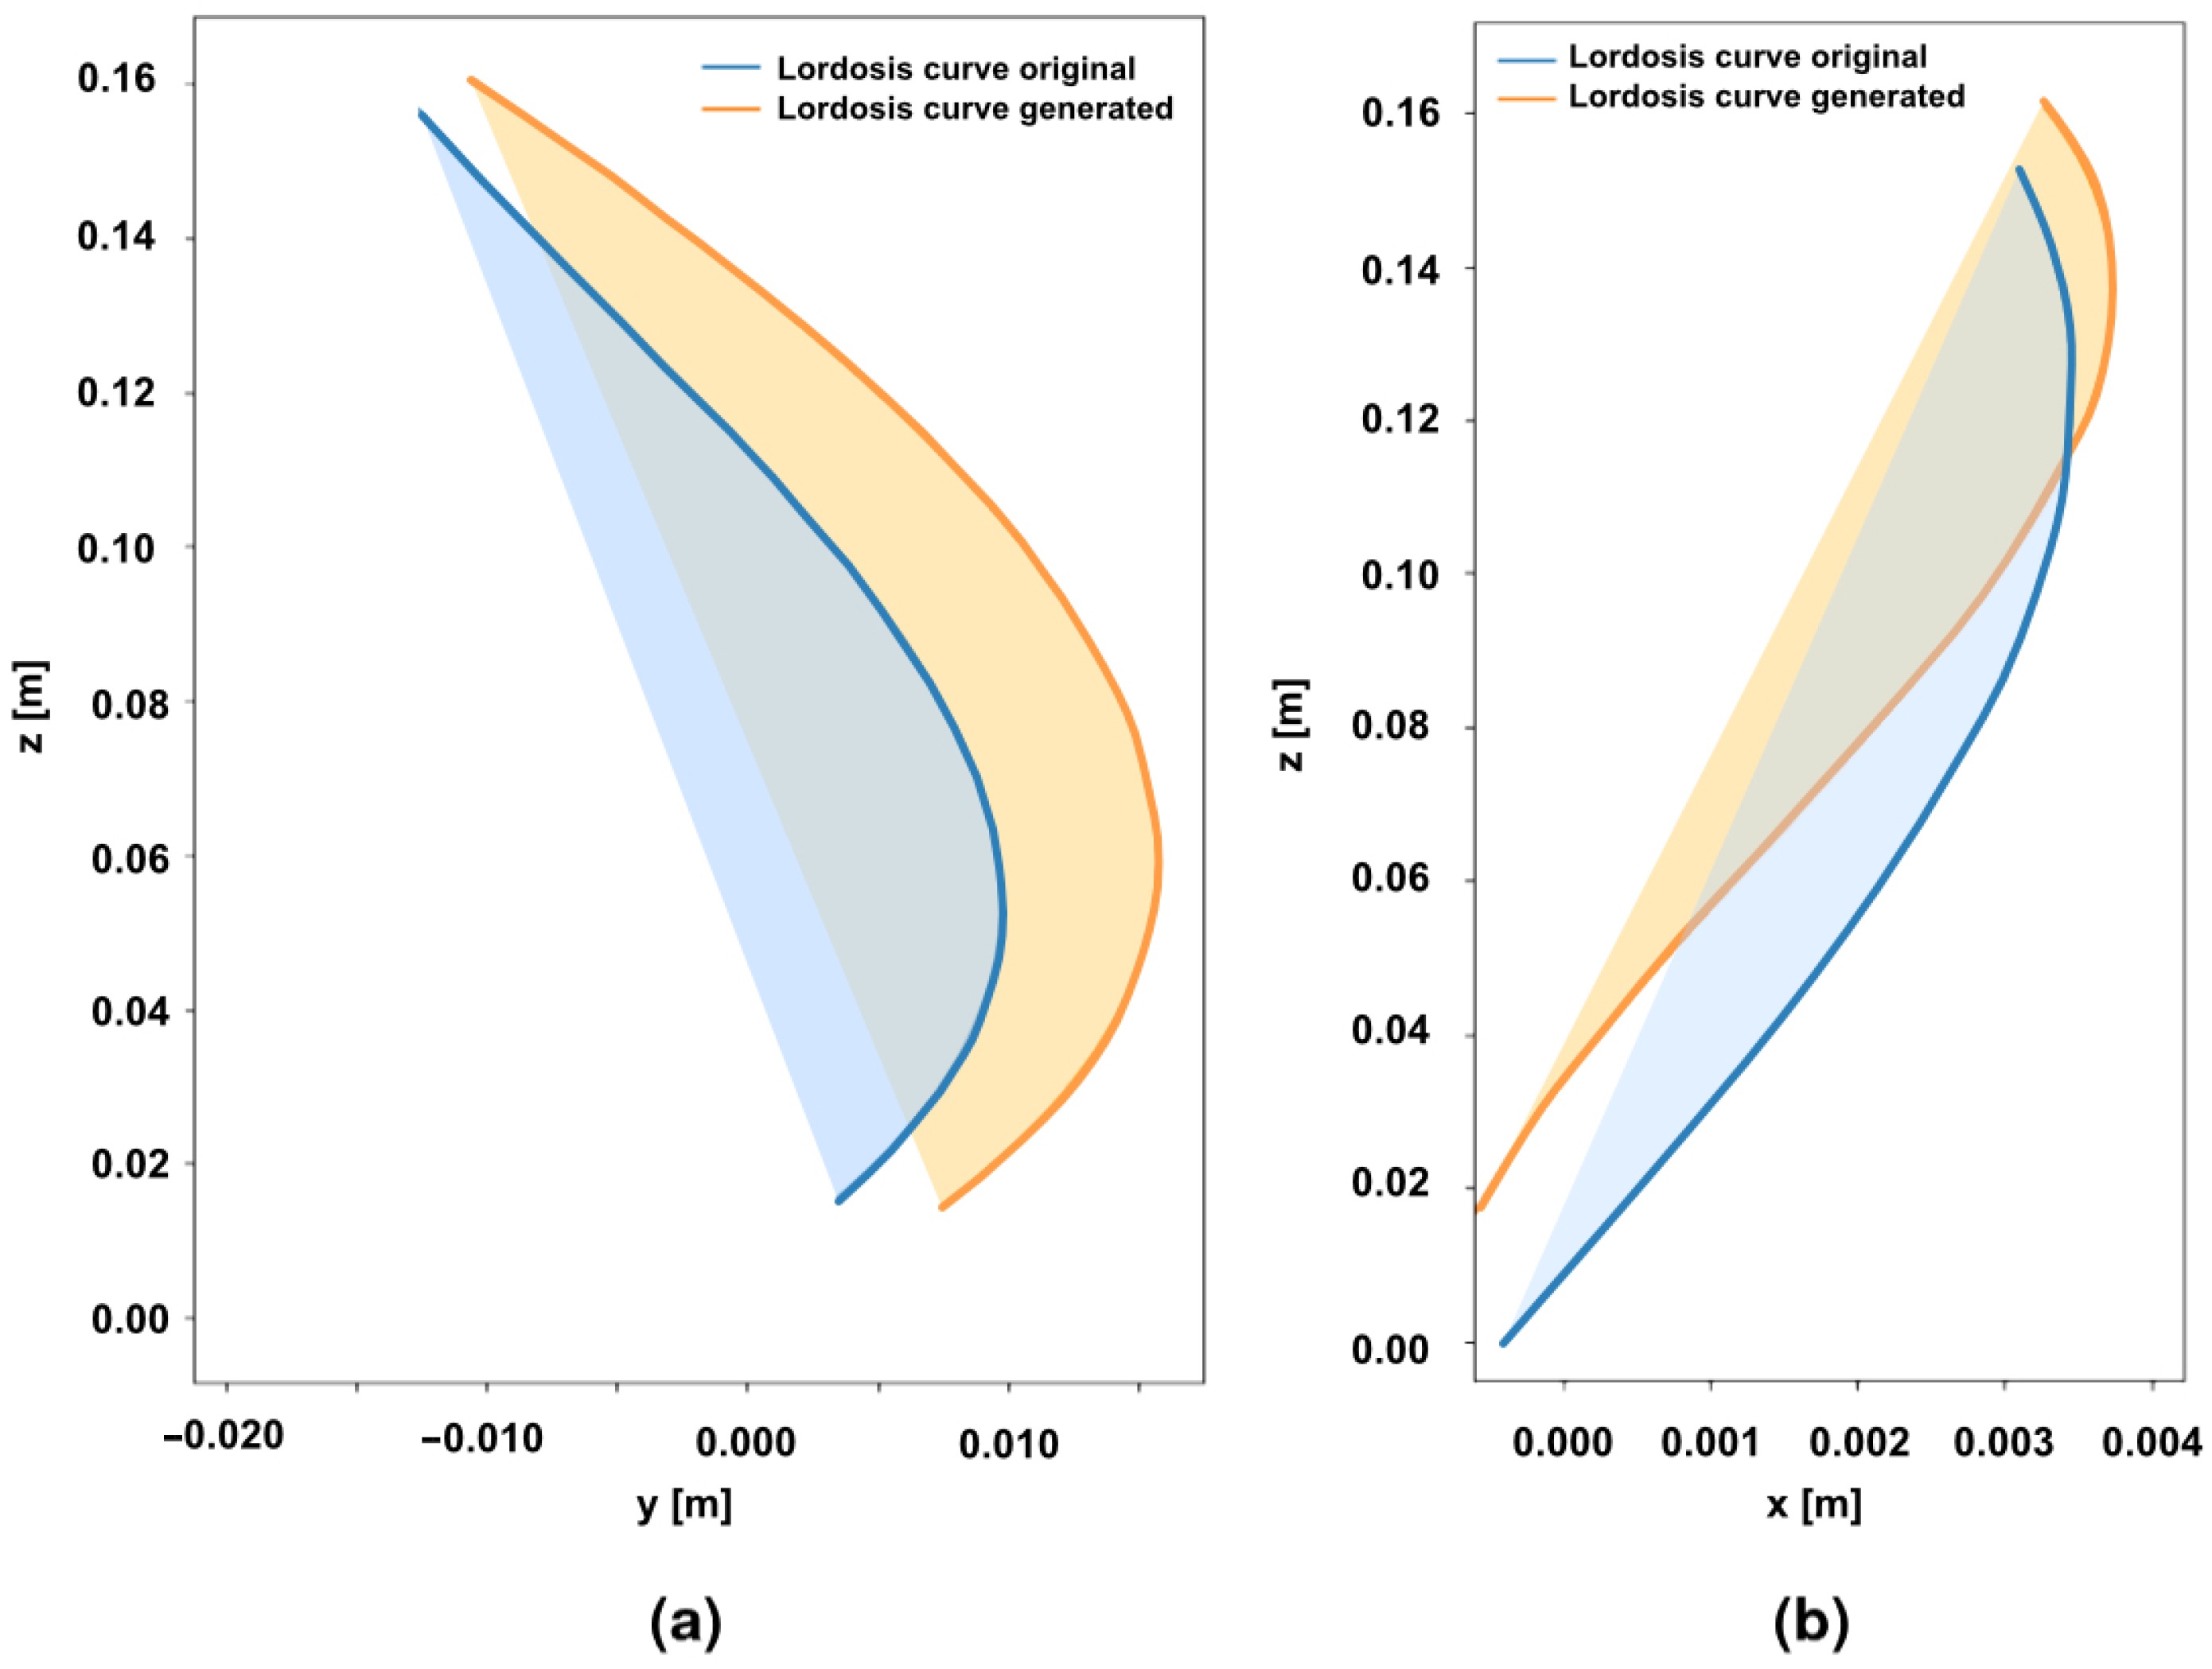

2.2. Lordosis Curvature Fitting for Simulation Model

3.2. Creation of New Lordosis Model from 3D Curvature